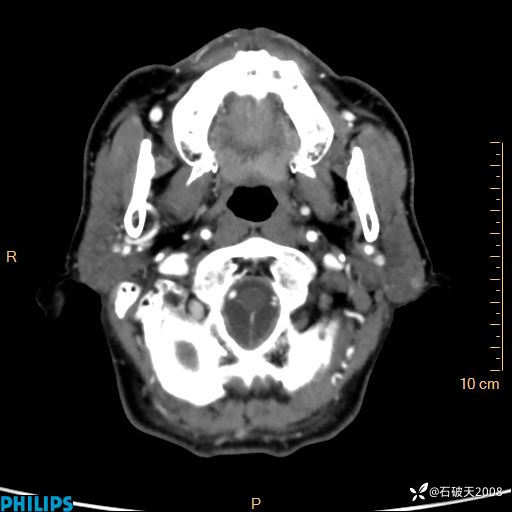

冠状位